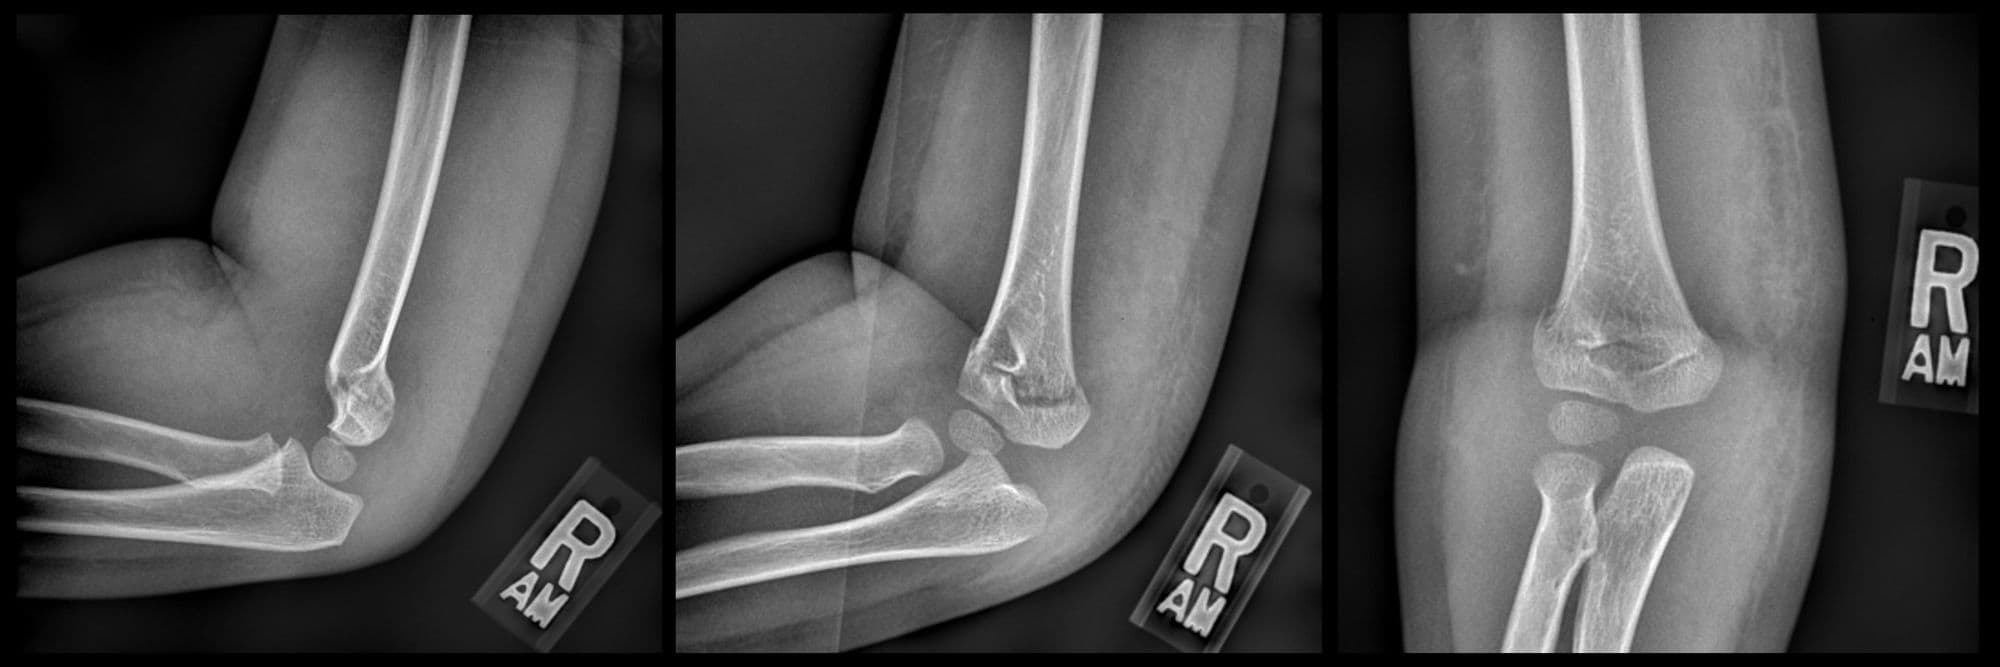

Supracondylar humerus CRPP